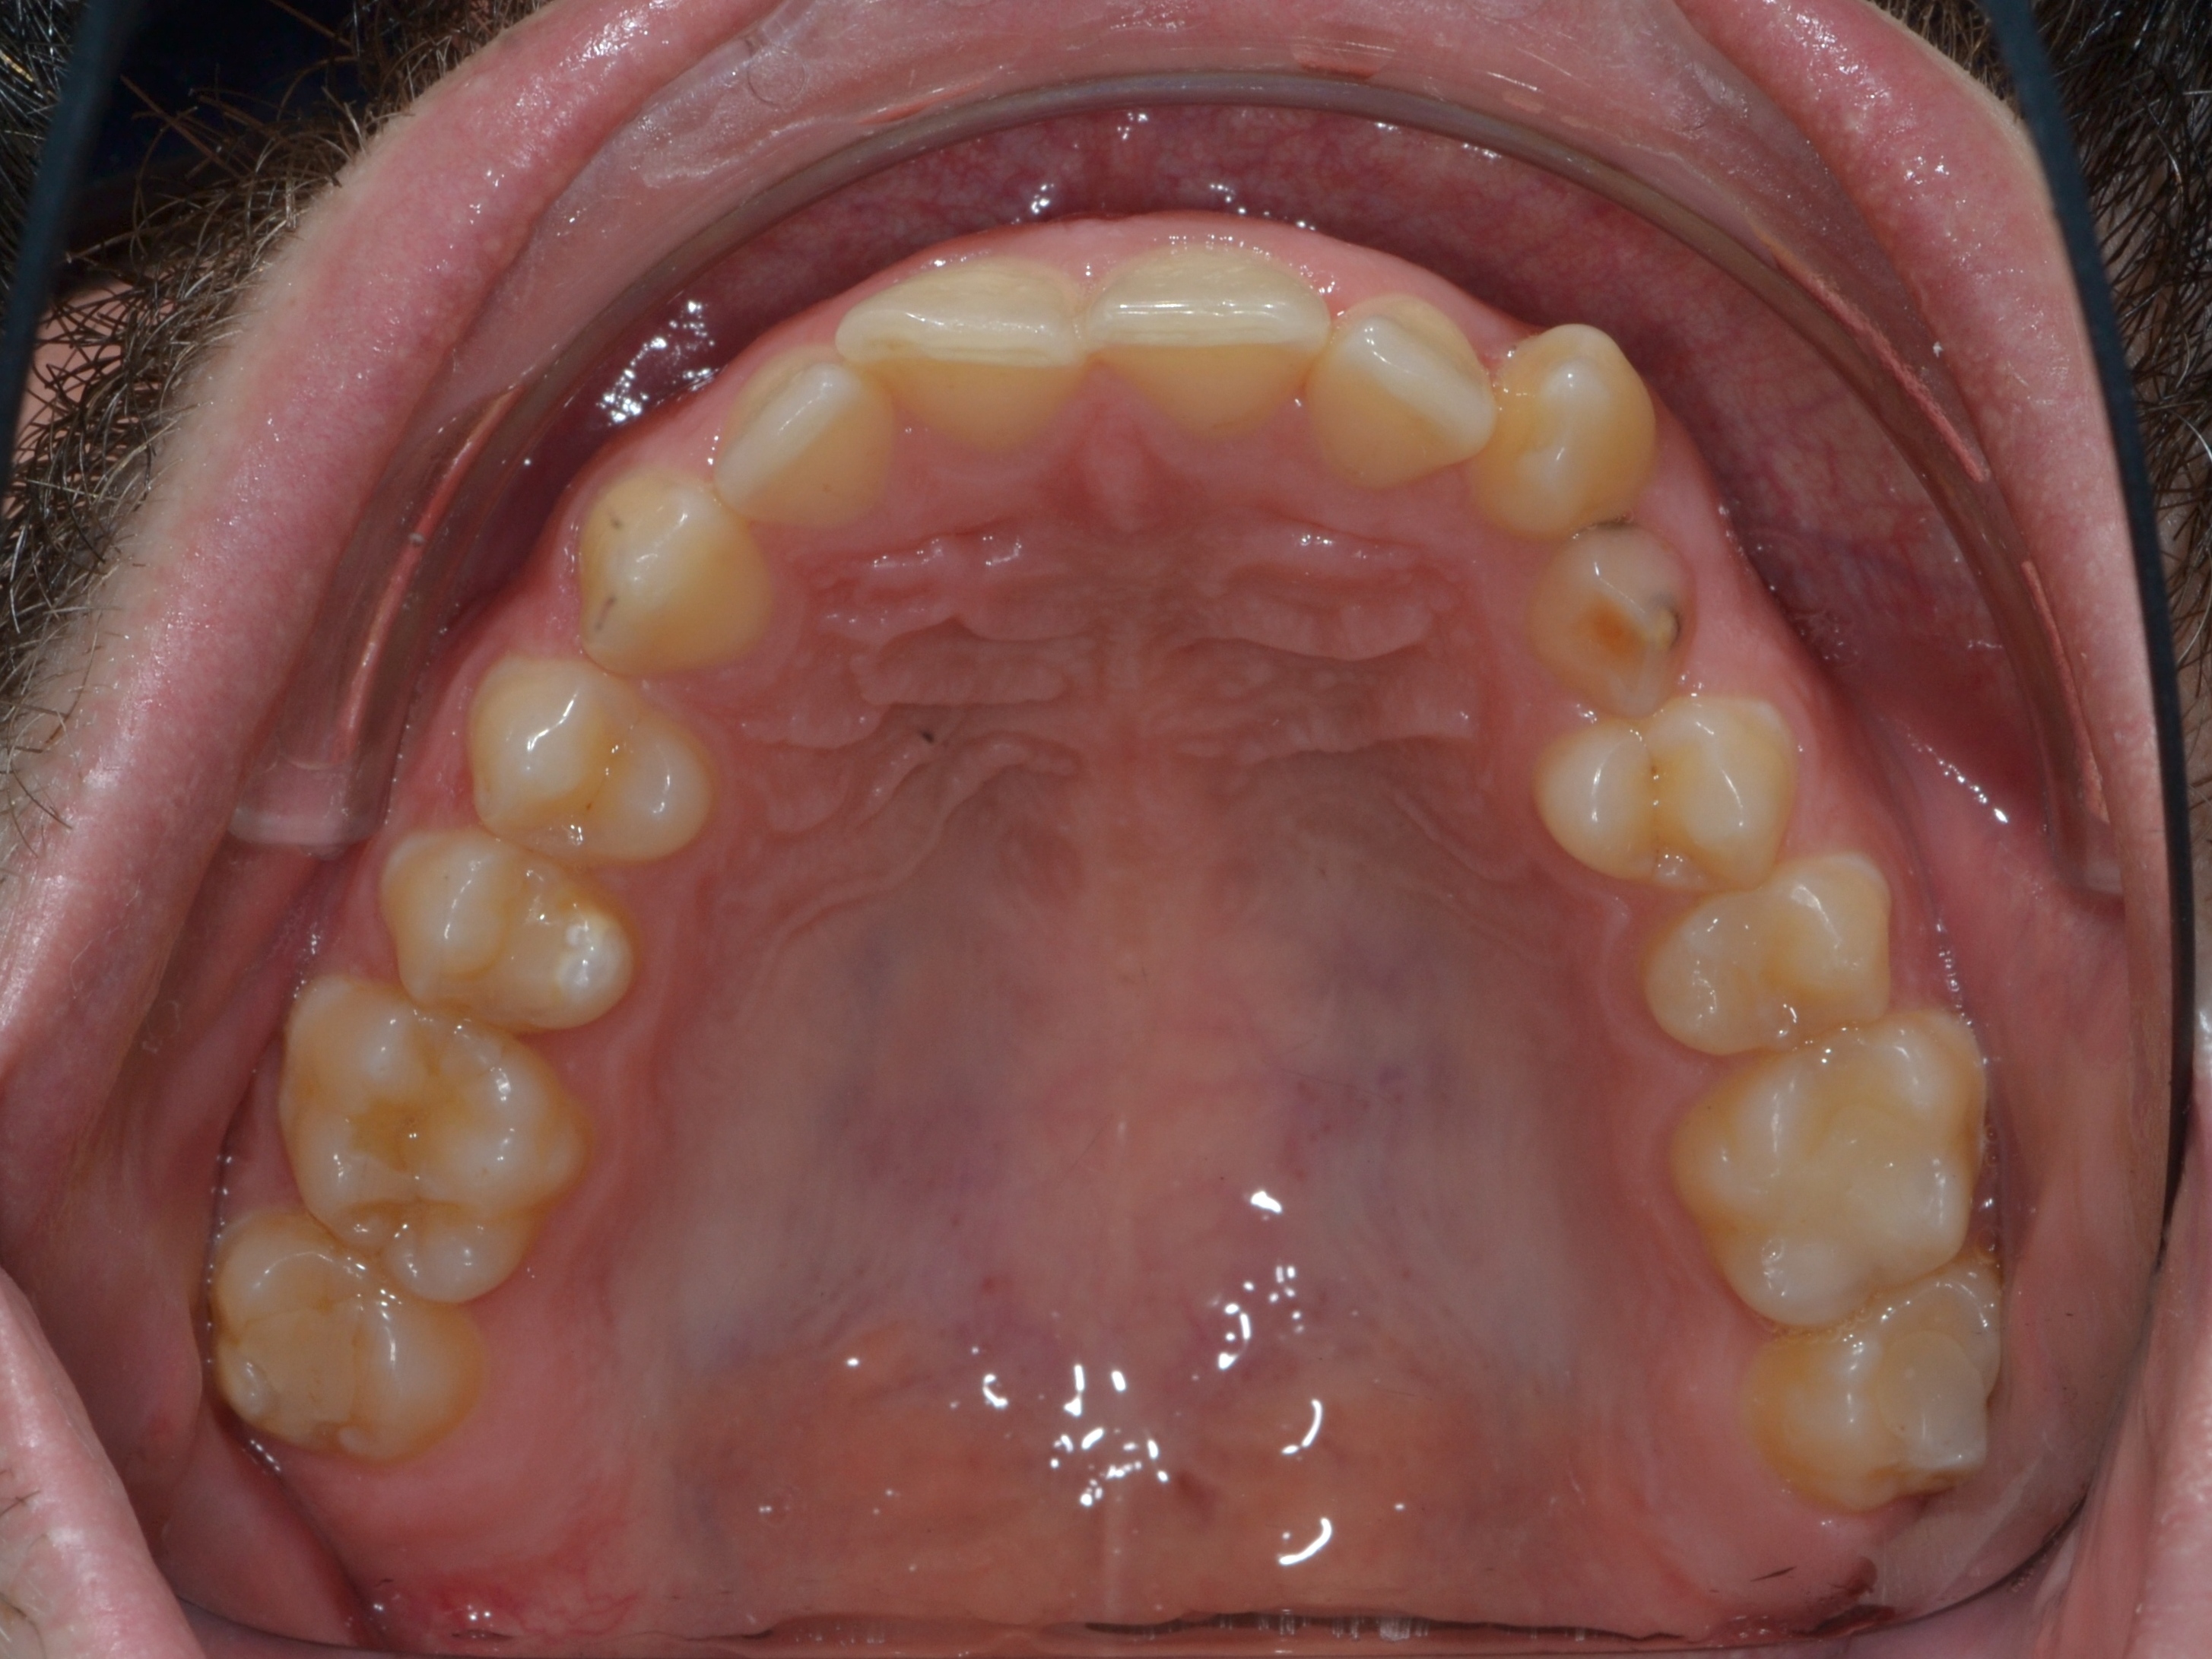

Выявленные проблемы

• Дистальная окклюзия ||(2)

• Глубокое резцовое соотношение

• Скученность фронтальных зубов

• Вестибулярное положение клыков

Брекет-система Ultra